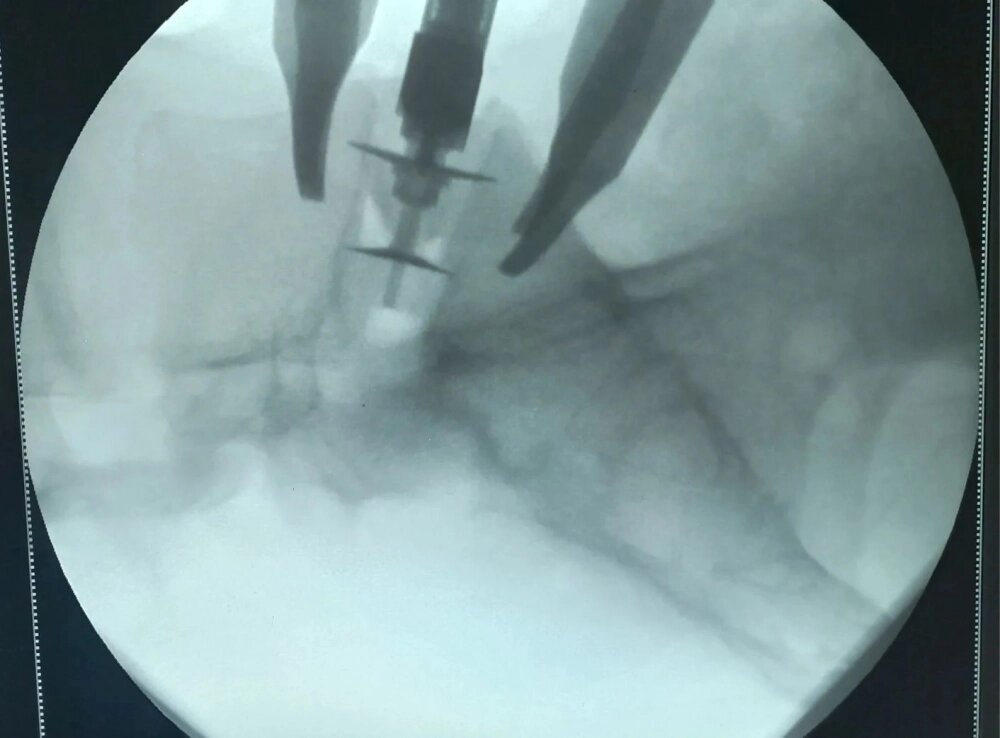

«ALIF — артродез позвоночника с передним внебрюшинным доступом — позволяет хирургу работать на передней части позвоночника и даёт возможность тотального удаления межпозвонкового диска», — поясняют в облздраве.

Во время операции используются имплантаты, фиксирующие позвонки в правильном положении. Они позволяют увеличить межпозвонковое расстояние и освобождают сдавленные нервные корешки. При таком подходе риск рецидива грыжи сводится практически к нулю.

На данный момент нейрохирурги ВОКБ № 1 Евгений Гридин и Игорь Корнилов выполнили три таких операции: два вмешательства на уровне L5—S1 и одно — на уровне L3—L4. У всех трех пациентов имелись грыжи межпозвонковых дисков, сопровождавшиеся сдавлением нервных корешков, что вызывало сильную боль в спине и ноге.